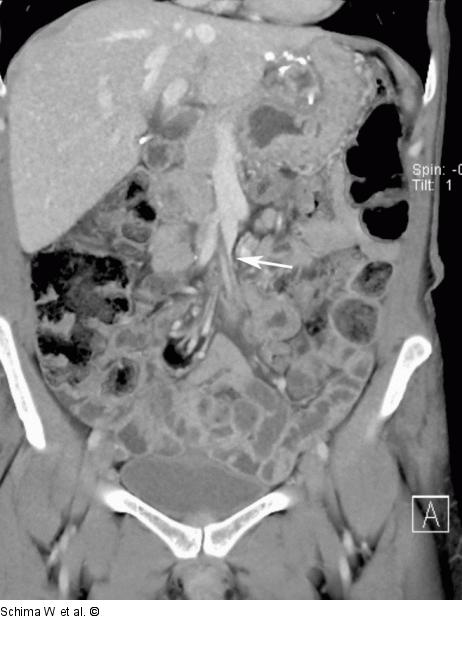

Abbildung 1d: MDCT Die V. mes. sup ist aufgrund der Torquierung des Mesenteriums mit Herniation von Dünndarmschlingen deutlich stenosiert (Pfeil |

Die V. mes. sup ist aufgrund der Torquierung des Mesenteriums mit Herniation von Dünndarmschlingen deutlich stenosiert (Pfeil |